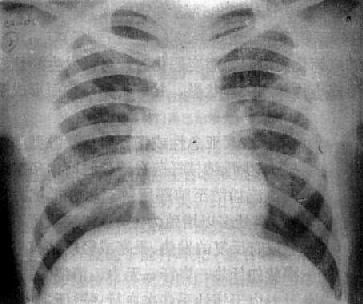

(1)一侧性肺不张:X线现为患侧肺野均匀致密,纵隔向患侧移位,肋间隙变窄(图3-1-7)。健侧肺可有代偿性肺气肿。

图3-1-7 一侧性肺不张

左侧支气管阻塞引起左侧全肺不张,显示左侧肺野均匀致密,

纵隔向患侧移位,肋间隙变窄,膈升高